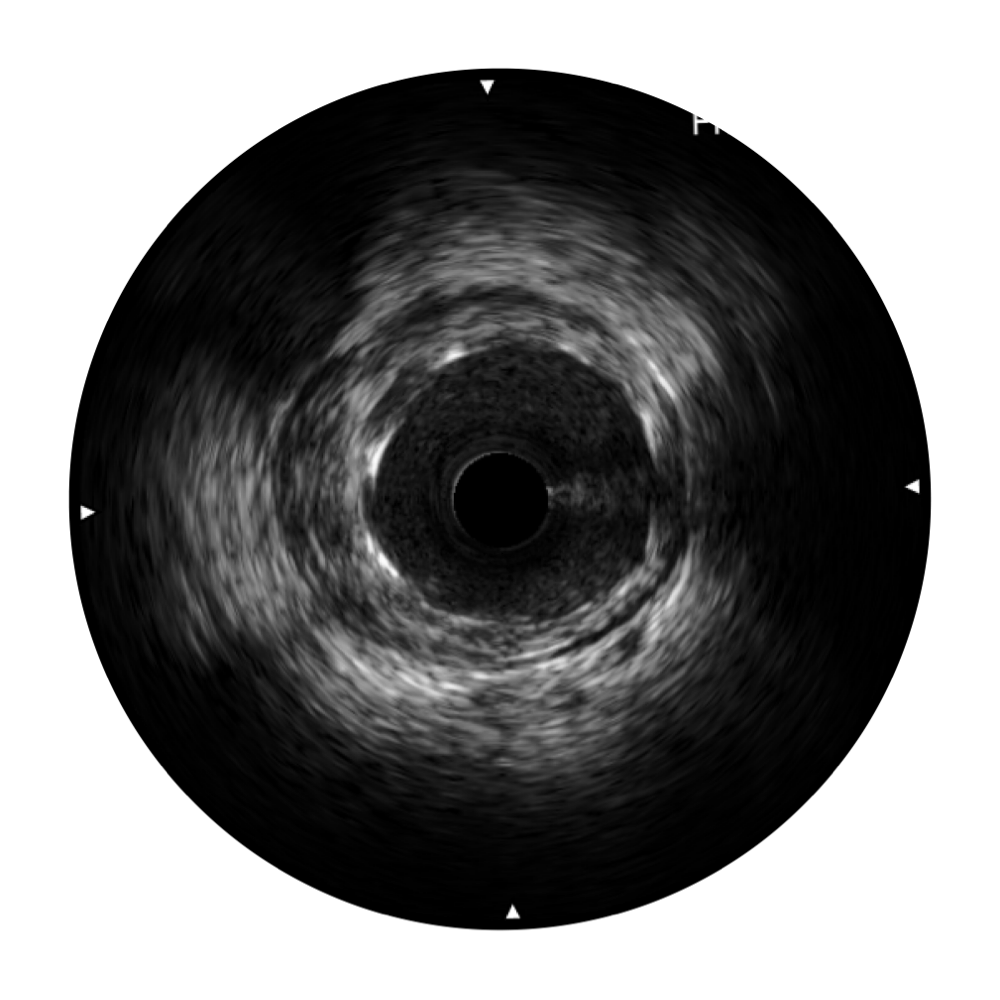

乐玩lewin国际宽频IVUS图像

传统IVUS图像

对比传统IVUS导管成像,乐玩lewin国际宽频IVUS图像的近场支架梁显影更细腻,远场中膜外血管仍清晰可辨,兼顾远中近,兼顾分辨力与穿透深度